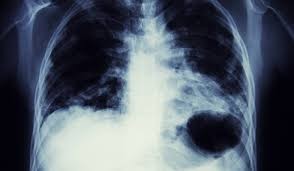

CANCERUL (2011-Rortaru Constantin) nu este altceva decât acumularea în o anumită zonă a organismului a Fe3+ sub formă de oxid de fier(III) negru care se poate vedea în stadiile mai evoluate ale bolii prin radiografii (țesutul nu permite trecerea radiațiilor X-este radioopac)după cum se vede în imaginea următoare: